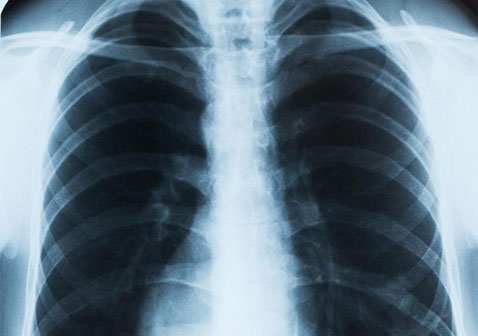

肺结核是由结核分枝杆菌引发的传染病,主要通过飞沫和空气在密切接触者之间传播。常见病征包括食欲不振、体重暴跌甚至咳血。卫生部强调,肺结核并非绝症,只要配合完成至少6个月的疗程,患者是可以完全康复的。